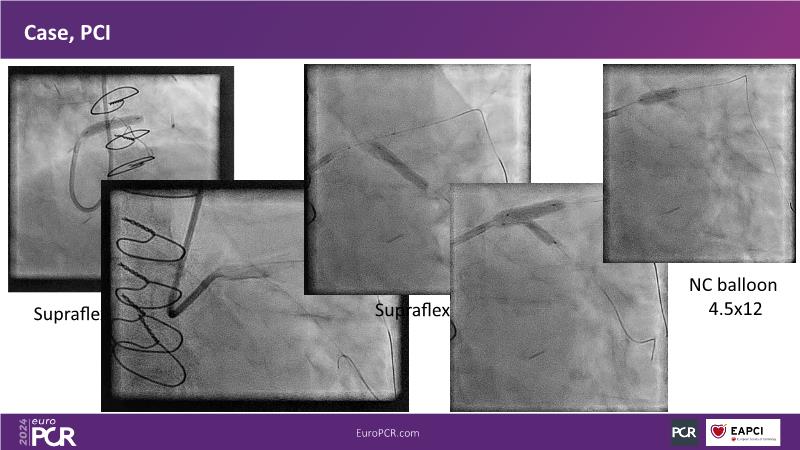

Discover the remarkable performance of Supraflex Cruz in real-world clinical settings, showcasing exceptionally low event rates and demonstrating its safety and efficacy across a spectrum of high-risk patients, including the elderly and those with high bleeding risks, and delve into the ongoing TALENT and TUDEXO II trials, designed to further elucidate the benefits of employing best PCI practices, particularly focusing on the efficacy of ultrathin struts such as Supraflex Cruz in managing complex CAD, including three-vessel disease, especially in diabetic populations.

- To learn that the treatment spectrum of Supraflex Cruz DES encompasses both simple and complex coronary artery disease (CAD)

- To learn the safety and efficiency of Supraflex Cruz across all patient strata (real world clinical practice; randomised control trials; elderly; high bleeding risk, diabetes)